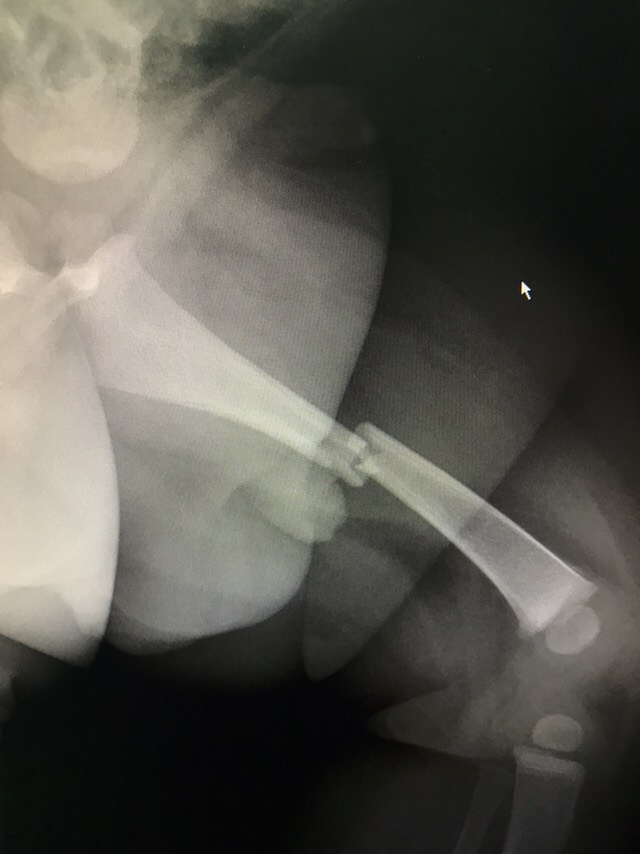

患者男性,6月。主诉:左腿疼痛、活动受限20小时。现病史:20小时前患者摔伤后左腿疼痛,拒按,形态异常,伴有活动受限,患儿反复哭闹不安,急诊于当地医院行x光检查提示:左腿股骨中段骨折,断端分离。现为进一步治疗,急诊以“左股骨中段骨折”收入我科。自患病以来,患者精神、食欲、睡眠一般,大小便基本正常,体重无明显变化。既往史无特殊。

查体:视:左腿肿胀,形态异常,未见明显皮下瘀斑,触:左腿明显肿胀、压痛,股骨不连续,可触及骨擦感,动量:左腿活动受限,其余肢体活动正常。辅助检查:我院x光提示:左股骨中段骨折、错位,软组织肿胀。

诊断:左股骨中段骨折。治疗:左股骨中段骨折复位内固定术。